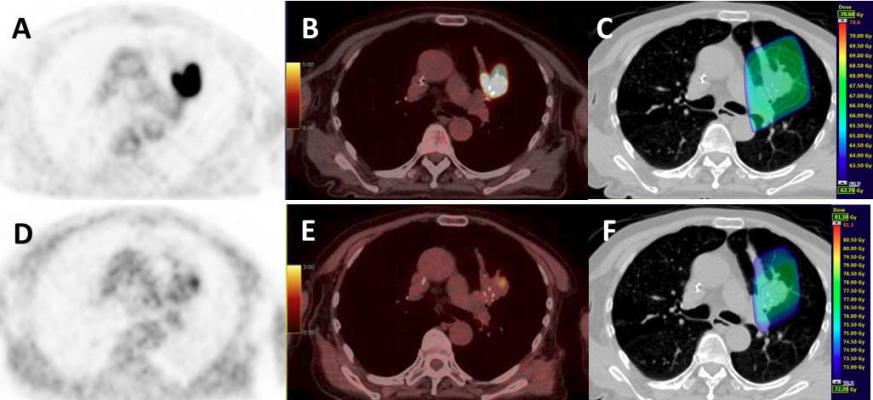

Image courtesy of Henri Becquerel Cancer Center

National guidelines recommend surgery as the first choice in treating early-stage lung cancer. An emerging treatment option is the use of precisely targeted radiation, sometimes referred to as stereotactic body radiation therapy (SBRT), to target tumors without surgery. The current analysis suggests that in early-stage lung cancer patients for whom recovery from surgery is predicted to be especially challenging (perhaps due to older age or underlying illnesses), SBRT may be a good option to lower the risk of post-treatment complications.